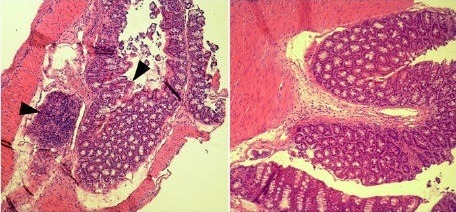

Em experimento, a inibição da prostaglandina E2 levou a um aumento na migração de células de defesa e produção de peptídeos antimicrobianos, resultando na redução da carga bacteriana no ambiente intestinal (imagem: comparação entre cortes microscópicos do tecido do cólon distal de ratos com infecção por C. rodentium e de ratos tratados com indometacina/ PNAS)

No experimento, um grupo de camundongos foi infectado por via oral com uma bactéria (Citrobacter rodentium), que mimetiza a infecção por E. coli em humanos. Depois de 24 horas, eles começaram a receber um tratamento de uma semana.

Alguns receberam uma substância inócua (controle) e outros indometacina a cada dois dias, ou diariamente L-161,982, antagonista do receptor E4 da prostaglandina E2. Ao fim do tratamento, foram analisados os intestinos de todos os camundongos.